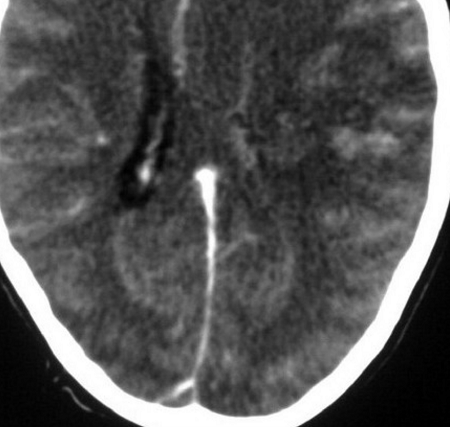

Picture: Contrast-Enhanced CT Brain

Name of Sign

Empty Delta Sign

Pathophysiology

The triangular shaped area that can be identified at the posterior pole of the head represents a filling defect due to the thrombus impeding blood flow.

Differentials

Dural venous sinus thrombosis (stroke)